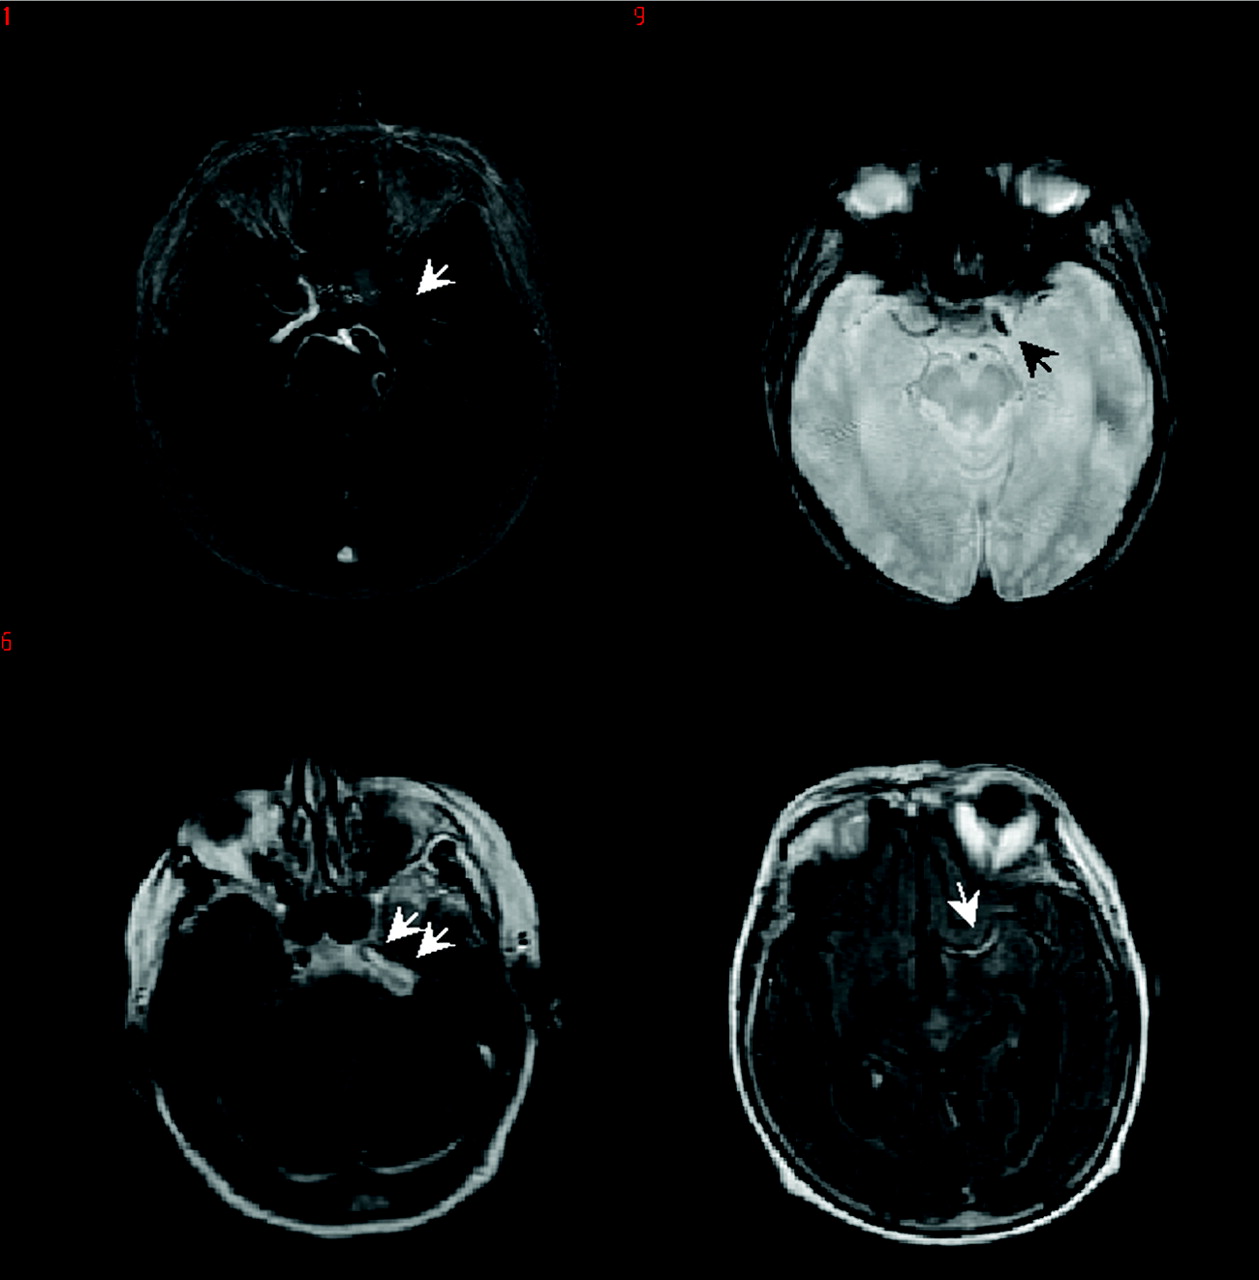

Assessment and congruence of localization of an occlusion (or no occlusion) was significantly associated and correlated for FLAIR HVS (two-tailed Pearson χ2, P < .001; SSR ρ, 0.66; Cramer’s V, 0.49, both P < .001), less significantly associated and correlated for CT HMCAS (two-tailed Pearson χ2, P = .018; SSR ρ, 0.56; Cramer’s V, 0.51, both P < .018) and not at all for the GRE SVS (all P not significant; SSR ρ, 0.18). For the 2-hour time point accuracy of occlusion localization was significant for FLAIR HVS (two-tailed Pearson χ2, P < .001; SSR ρ, 0.73; Cramer’s V, 0.72, both P < .001) and less for the GRE SVS (two-tailed Pearson χ2, P < .001; SSR ρ, 0.29, Cramer’s V, 0.45, both P < .05). At 24 hours, the values were (two-tailed Pearson χ2, P < .001; SSR ρ, 0.61, Cramer’s V, 0.71, both P < .001) for FLAIR HVS and (two-tailed Pearson χ2, P < .001; SSR ρ, 0.43, Cramer’s V, 0.55, both P < .001) for GRE SVS. In all instances, where the localizations assessed on GRE and FLAIR did not match those on MRA/PWI, the occlusion was located more distally than on MRA/PWI. This was, however, more frequently the case on GRE (7/15) than on FLAIR (9/27) (Figure 1).

An 82-year-old female patient with cardioembolic stroke, baseline NIHSSS of 18 received rt-PA 88 minutes after symptom onset. Stroke MR imaging at 40 minutes after symptom onset. MRA (upper left) shows left-sided ICA occlusion extending into the MCA (arrows). This occlusion is seen on GRE (upper right, arrows) as a GRE SVS only at the level of the MCA, a FLAIR HVS can be seen at the level of the ICA and MCA (lower row, arrows).